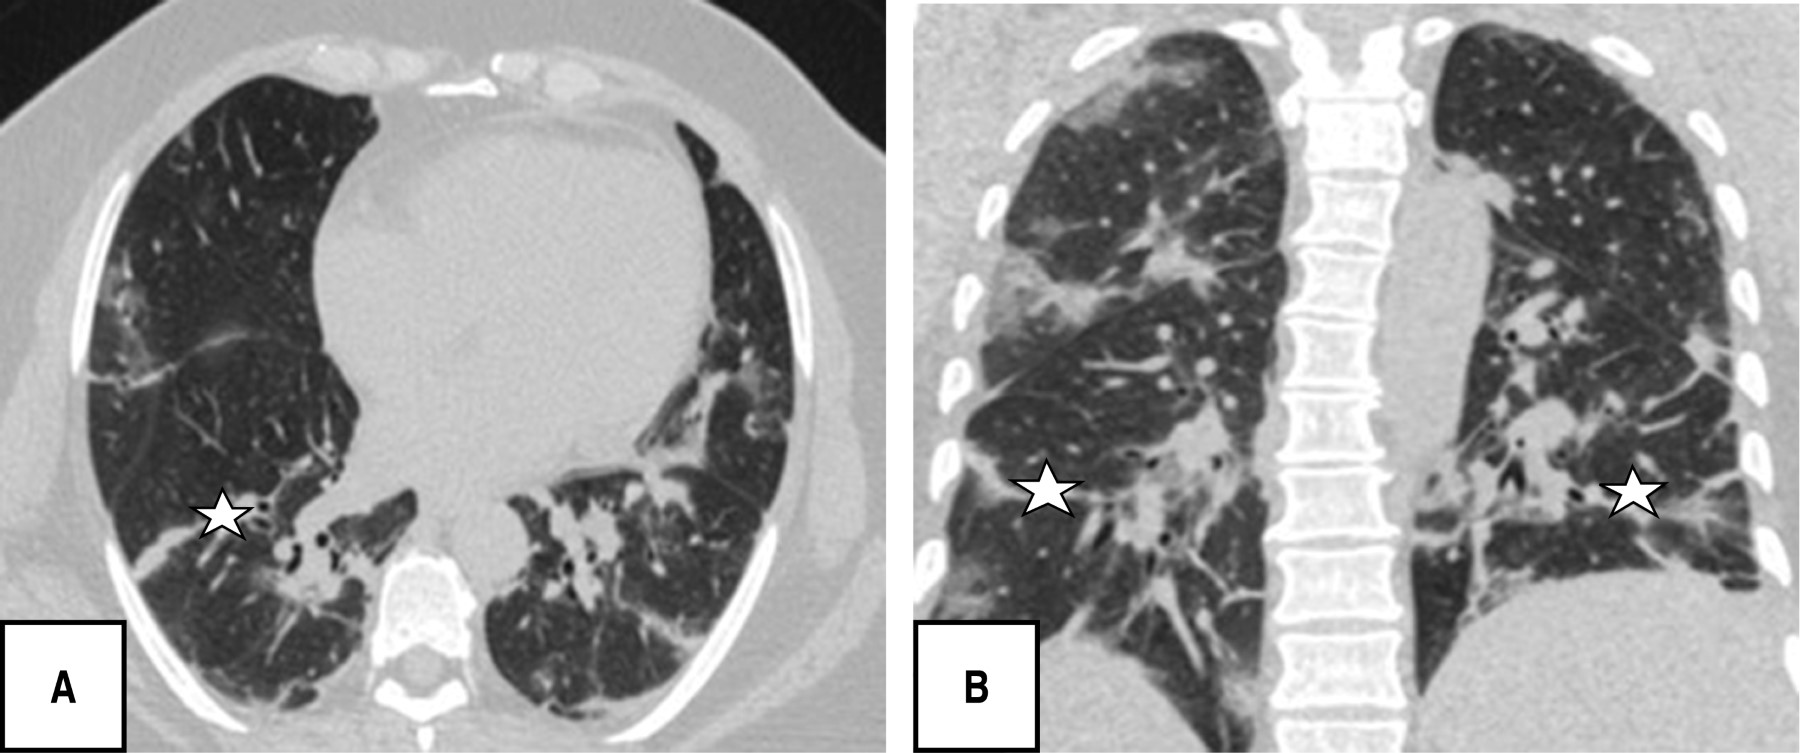

During the tomographic evaluation, the most frequent pulmonary patterns were: cobblestone pattern (120 [80.5%]), pleuroparenchymal bands (118 [79.2%]) and ground glass pattern (110 [73.8%]), reticular pattern (82 [55%]), and in lower percentage vascular dilatation (56 [37.6%]) and consolidated pattern (52 [34.9%]) (Figures 1, 2, 3 and 4).

Each patient was found to have five of five lung lobes affected, 144 (96.6%), with a total percentage of involvement of 26-49%, (96 [62.4%]); the most characteristic distribution of lung involvement was central and peripheral (86 [57.7%]), and without segment predominance (86/57.7%) followed by localization in posterior segments (59/39.6%), all with statistical significance (p < 0.05). The PATPAS severity score presented by the patients was moderate (93 of 149 patients [62.4%]).

It is noteworthy that most of the patients in this research presented in a chronic/advanced phase of the disease, finding as predominant patterns the cobblestone (120/149; 80.5%), pleuroparenchymal bands (118/149; 79.5%) and in third place ground-glass pattern (110/149; 73. 8%), without identifying any case with findings of atoll, pneumothorax or twinning tree, other studies do report ground glass opacities as the predominant finding followed by the consolidation pattern and in this regard pleural effusion, pericardial effusion, lymphadenopathy, cavitation, the reverse halo or atoll sign and pneumothorax are rare, but can be observed with the progression of the disease.19-21

Segmental involvement was without predominance and with a central and peripheral distribution in equal percentage with 57.7%, different to that published by Pan F et al., where the lower lobes were more likely to be involved and in general, the subpleural distribution of lesions was more frequent than central lung lesions.22